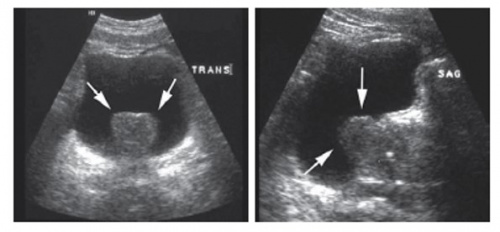

정상 전립선 소견. (a-c) transverse view, (d) sagittal view.

SV; seminal vesicle, CZ; central zone, TZ; transitional zone, PZ; peripheral zone,B; bladder, U; urethra

• 전립선 크기 측정

TRUS의 가장 큰 목적 중에 하나는 전립선의 크기를 측정하는 것이다. Transverse view에서 너비(width)와 높이(height)를 측정하고 sagittal view에서 길이(length; bladder neck ~ apex)를 측정한 후 편장형타원체공식(ellipsoid volume formula)을 이용하여 계산한다.

전립선 용적 = Ω/6 x H x W x L (Ω/6 ≈ 0.523)